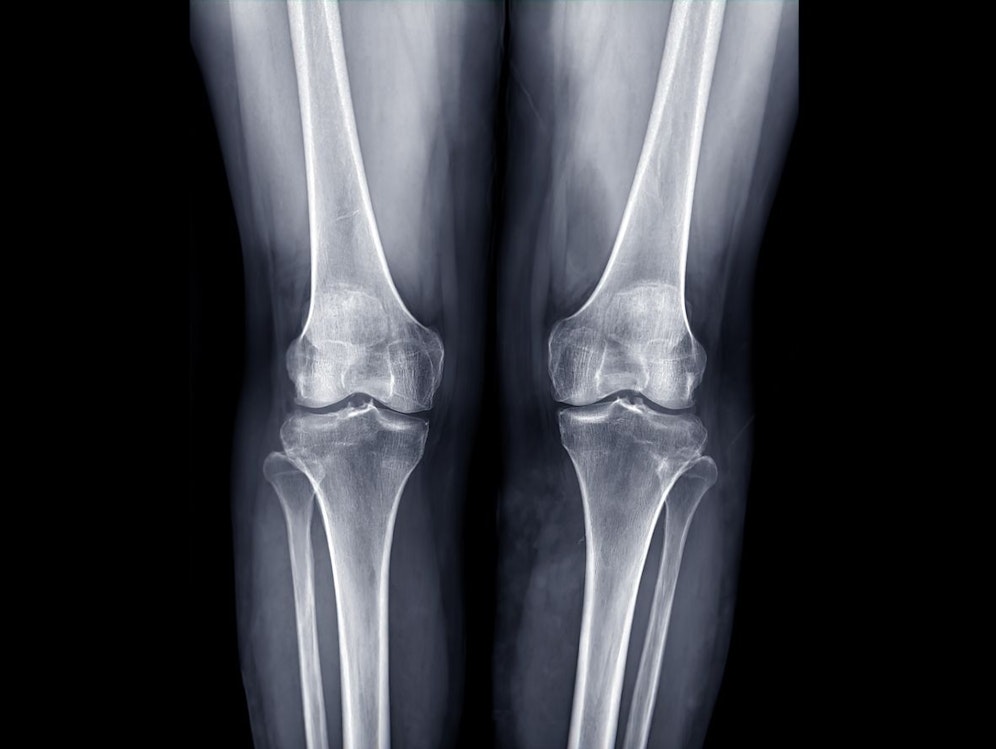

Einem Bericht des "Daily Star" zufolge bezahlte Conn 130.000 Pfund (148.772 Euro) für eine Beinverlängerungsoperation, bei der ihm beide Oberschenkelknochen gebrochen wurden, um zehn Zentimeter größer zu werden. Der gebrochene Knochen wird mit Verlängerungsmarknägeln fixiert. In Folge bildet der Körper eigenes Knochenmaterial und füllt den Bruch damit auf – der Knochen wächst also.